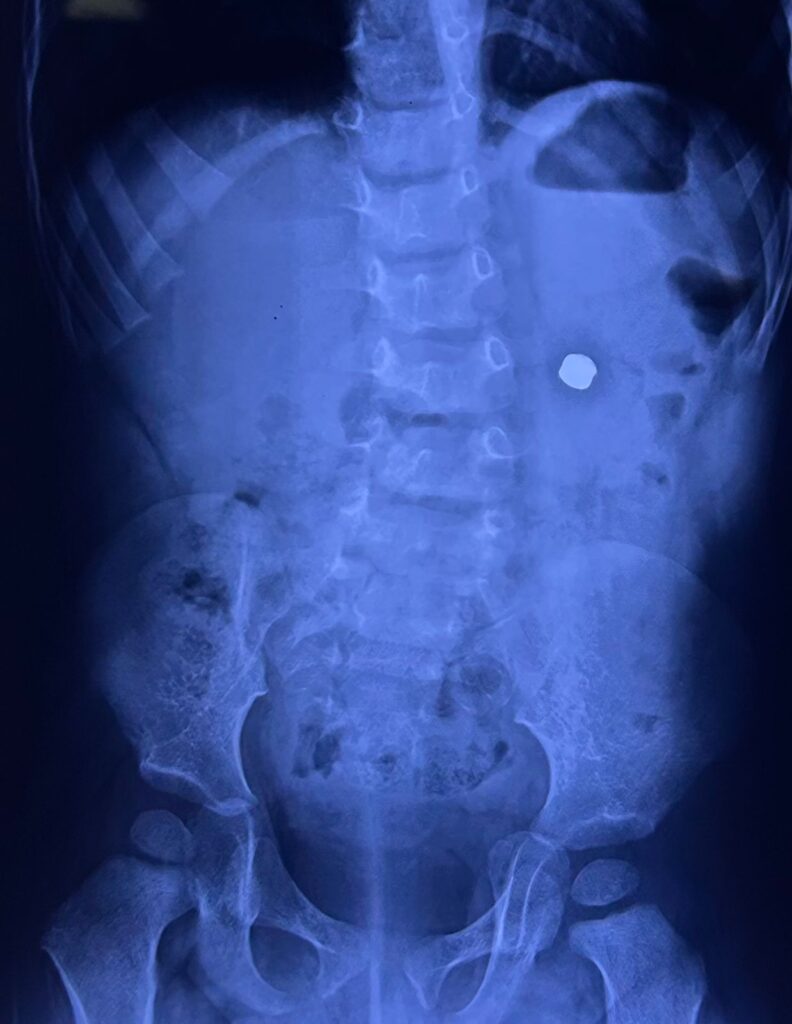

Baby Agastya was brought to the hospital with green vomiting and stomach pain on 2nd May 2025. An X-ray showed a foreign object in the stomach. Doctors tried to remove it through endoscopy the same night, but the battery had already lodged deep in the stomach wall and couldn’t be taken out safely that way.